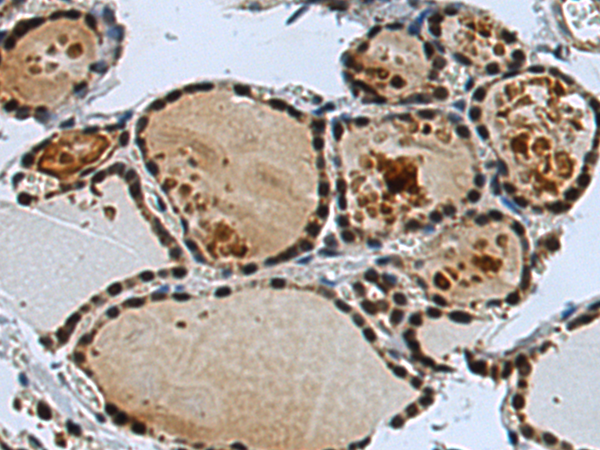

分类: 科研抗体货号: P10203别名: RaLP; SHCD应用: IHC反应种属: Human